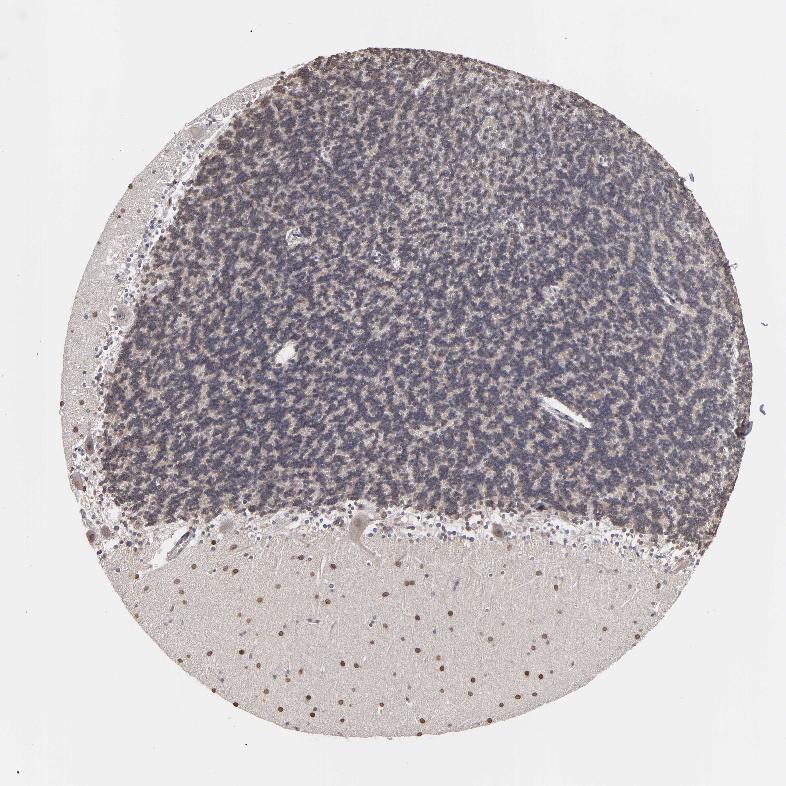

CEREBELLUM - Antibody stainingi

Antibody staining in the annotated cell types in the current human tissue is reported as not detected, low, medium, or high, based on conventional immunohistochemistry profiling in selected tissues. This score is based on the combination of the staining intensity and fraction of stained cells.

Each image is clickable and will lead to virtual microscopy that enables deeper exploration of all samples and also displays staining intensity scores, fraction scores and subcellular localization as well as patient and tissue information for each sample.

Antibody HPA002980

Purkinje cells Medium

Cells in granular layer Medium

Cells in molecular layer High